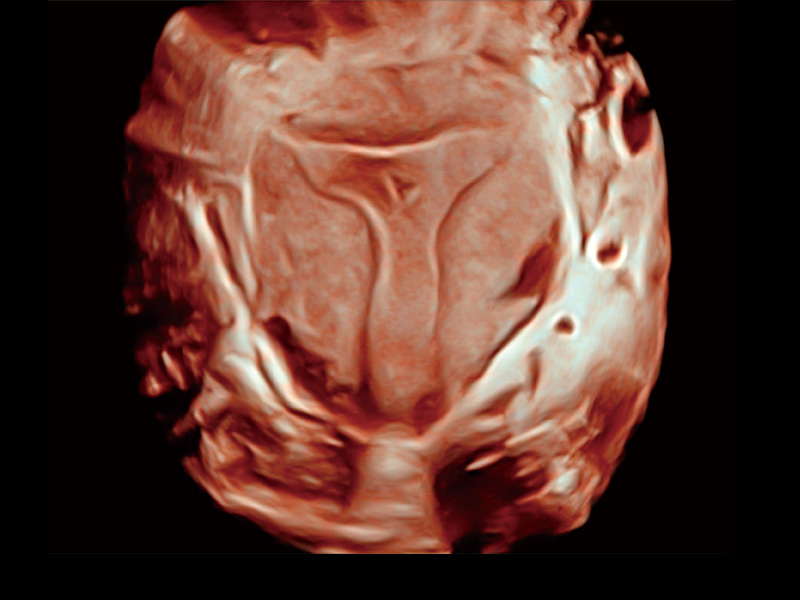

腔内容积探头

腔内三维成像技术获得显著提升,超大扇角在满足日常基础扫查的同时,支持卵泡自动测量及多种三维渲染模式,为您提供更多的诊断信息,尤其是在子宫畸形的诊断,内膜及肿瘤占位观测中起到了重要的作用。

卵巢多囊样改变

单角子宫